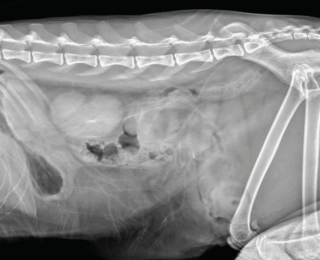

Pelvic trauma is a common finding in feline blunt-trauma patients and survey radiographs are recommended, even in ambulatory cats (Figure 9). Crepitus on manipulation of the pelvic limbs or palpation of fractures directly via rectal examination can provide an initial indication. Sacroiliac, coxofemoral and distal joint luxations, as well as long bone fractures are also fairly common and may be evident on physical examination or can be assessed on survey radiographs. The abdomen should also be carefully palpated for subtler abdominal wall ruptures (Figure 10).